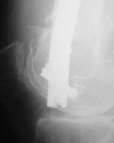

KEMMD> Again, Locking Plating is minimally invasive, SUBCUTANEOUS

KEMMD> INTERNAL FIXATION

Characteristic of locking nailing hardly ever sounds less attractive...

KEMMD> and I believe for the most surgeons preferred

KEMMD> method of treatment for distal femur fractures

A new toy is more interesting and fashionable. And anyway it is not panacea, i have already seen presentations with LISS failures like the attached one presented by D.Seligson. And people also demonstrated incisions say that the method is not so LESS invasive as it supposed to be.